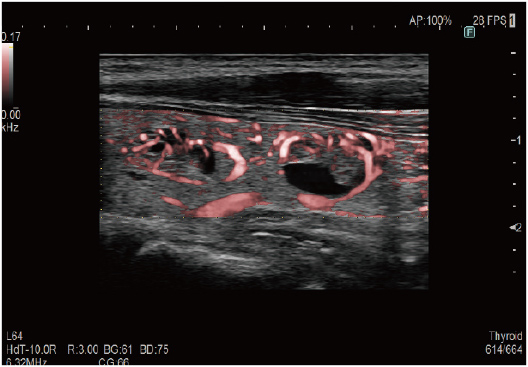

In addition to the sensitivity improvement, homogenous images can be acquired with high resolution in wider area of display. It is expected to prevent the overlook of information in wide area observations. eFocusing PLUS has enhanced tissue delineation performance as a result of its transmission beam design change and evolution of receiving technology.

Tissue structures such as vessel wall can be delineated clearly keeping the texture and the expression of surrounding tissue. The evolved edge emphasis processing technology can extract the structures effectively.